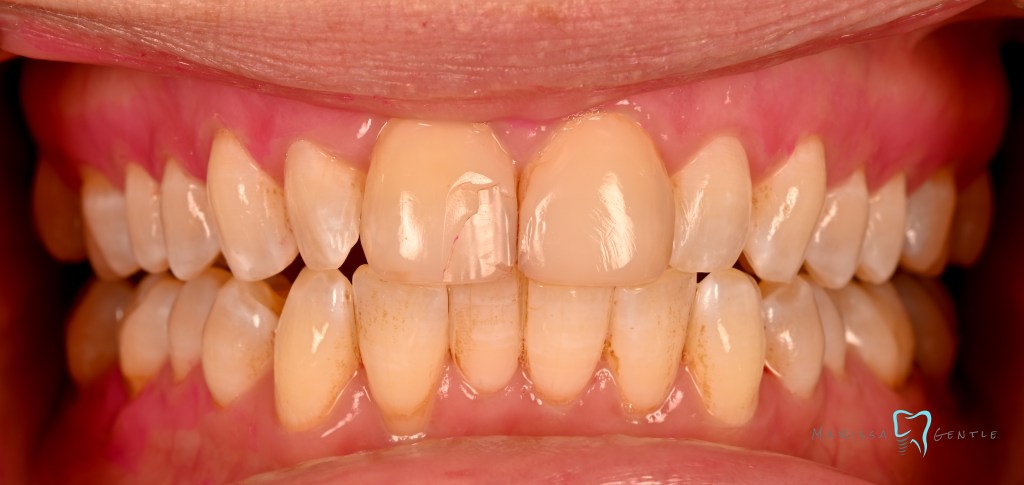

Patient presented with esthetic concern, composite veneers were placed 3 years prior. Patient’s chief complaint is twisted #7, thickness of the composite veneers and now chipping. The veneers were placed initially due to Enamel hypoplasia. Clinically relevant information: the patient wears a mandibular advancement device as treatment for sleep apnea, malocclusion noted edge to edge. Zirconia crowns planned #7-10

Current composite veneers are defective and caries are clinically present